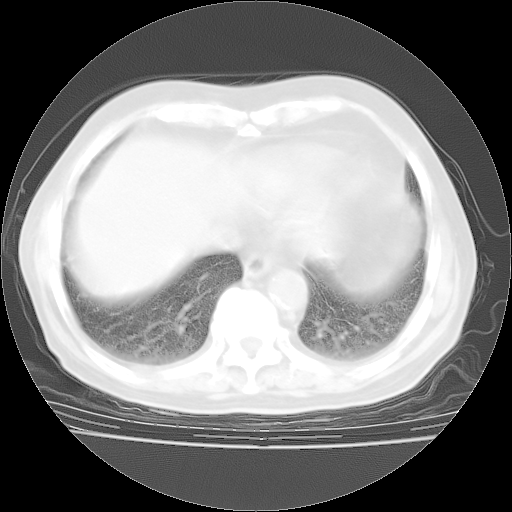

4月28日肺部CT——再次出现类似去年5月9日——透光度降低,“间质性”改变。

4月28日肺部CT——再次出现类似去年5月9日——磨玻璃样、间有“粟粒样”改变。

4月28日肺部CT

个人阅读4.14日肺部CT平扫:纵隔窗无异常,但肺窗示:双下肺内、后基底段有片絮状侵润影,部位以后基底段为著,以间质改变为主,呈急性肺泡炎征像,和首次住院影像学有相似之处。仅是个人读片,明日请相关专家再读片哈。其它建议同上。